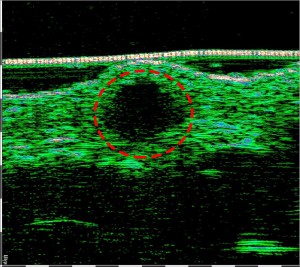

-Υπέρηχος Υψηλής Συχνότητας (HFUS) και Ιστολογία

-Κύριες εφαρμογές

-Κύριες παθολογικές διεργασίες

-Γενικά πεδία εφαρμογής ογκολογίας

-Απλά διαγνωστικά κριτήρια κακοήθειας όγκου δέρματος